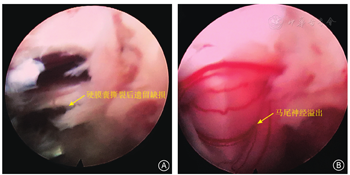

PIED一般只会损伤椎管内的神经。有学者采用局部麻醉下穿刺至突出物、直接扩张置管摘除髓核的方法,需要依赖患者的疼痛反馈,但仍难以规避损伤神经的风险。温冰涛等[8]报告689例患者中2例神经根损伤均发生在PIED术中。Ruetten等[9]采用切开黄韧带逐步进入椎管的方法,可减少神经及硬膜囊损伤的概率,已得到广泛应用。PIED进入椎管后如果神经张力过大,可能会被压扁呈薄膜状贴在突出物表面,在二维空间下操作分辨不清或视野不清时可能连同椎间盘一起被髓核钳钳夹损伤,所以术中应及时止血、保持清晰的视野,除髓核已溢出者外,摘除突出物前需确认其表面无神经覆盖,可用神经钩仔细分离并推开神经,避免盲目钳夹。我们采用逐步切开黄韧带法进入椎管手术400余例,仅早期1例用髓核钳咬除黄韧带时咬伤神经根外膜,但未损伤神经纤维,致伤原因与两者贴合紧密有关;突破黄韧带后在水介质下可清晰显露神经根和硬膜囊,分离牵开神经后显露椎间盘突出,可避免盲视下穿刺、置管对神经的损伤;L 5S1节段神经根腋下或中央突出者可自神经根腋下进入,其他外侧型突出可在清除神经根背侧黄韧带后,自神经根肩上进入,避免增加神经根腋下与硬膜囊之间的张力。

PTED在盲视下扩大椎间孔、PIED在盲视下置管均可损伤硬膜囊,内镜下摘除过程中分辨不清、盲目钳夹、突出物与硬膜囊粘连紧密也可损伤硬膜囊,导致脑脊液漏。随着PTED从椎间盘内间接减压到椎管内直接减压、以及复杂病例的增多,硬膜囊撕裂的发生率增高,大多发生在摘除阶段,但此并发症的发生率多被低估。由于经皮内镜在生理盐水压力灌洗下操作,小的撕裂神经未疝出时难以发现;较大撕裂时神经根和马尾神经也不一定马上溢出,可随水压变化而进出硬膜囊裂口。硬脊膜撕裂可导致颅内压增高,部分患者出现头痛、项背痛,甚至个别患者出现抽搐、四肢运动和感觉功能暂时性丧失等,因此,当发生硬膜囊撕裂时应尽快结束手术、降低水压,避免射频电极损伤神经纤维。由于PTED手术空间小、部位深,术后不像开放手术那样容易引起较多脑脊液漏、局部肿胀、头痛、头晕等症状;但如果神经纤维自硬膜囊破口溢出后可造成神经嵌顿或卡压,可导致剧烈的放射性疼痛,呈电击样,活动时加重,MR检查一般无明显的再突出和压迫,但可有脑脊液漏的继发影像,如神经根疝、椎间隙内脑脊液积聚等,保守治疗常无效,需开放手术探查,回纳嵌顿的神经纤维、修补缝合硬膜囊裂口。Ahn等[10]报告816例PTED患者中9例(1.1%)发生有症状的硬膜囊撕裂,但在术中发现仅3例,出现脑脊液漏和头疼、背痛,即转为开放手术修补;另6例术中未发现,术后出现腿疼,均行开放手术探查(2例神经根自硬膜囊撕裂处疝出,患者有神经损害症状,其中1例行融合手术,但随访时效果均较差;4例神经根无疝出,无神经损害症状),但其中只有2例偏外侧的撕裂可以修补,其余4例靠近中央腹侧的撕裂无法缝合,只能应用纤维蛋白胶等材料封堵填塞。